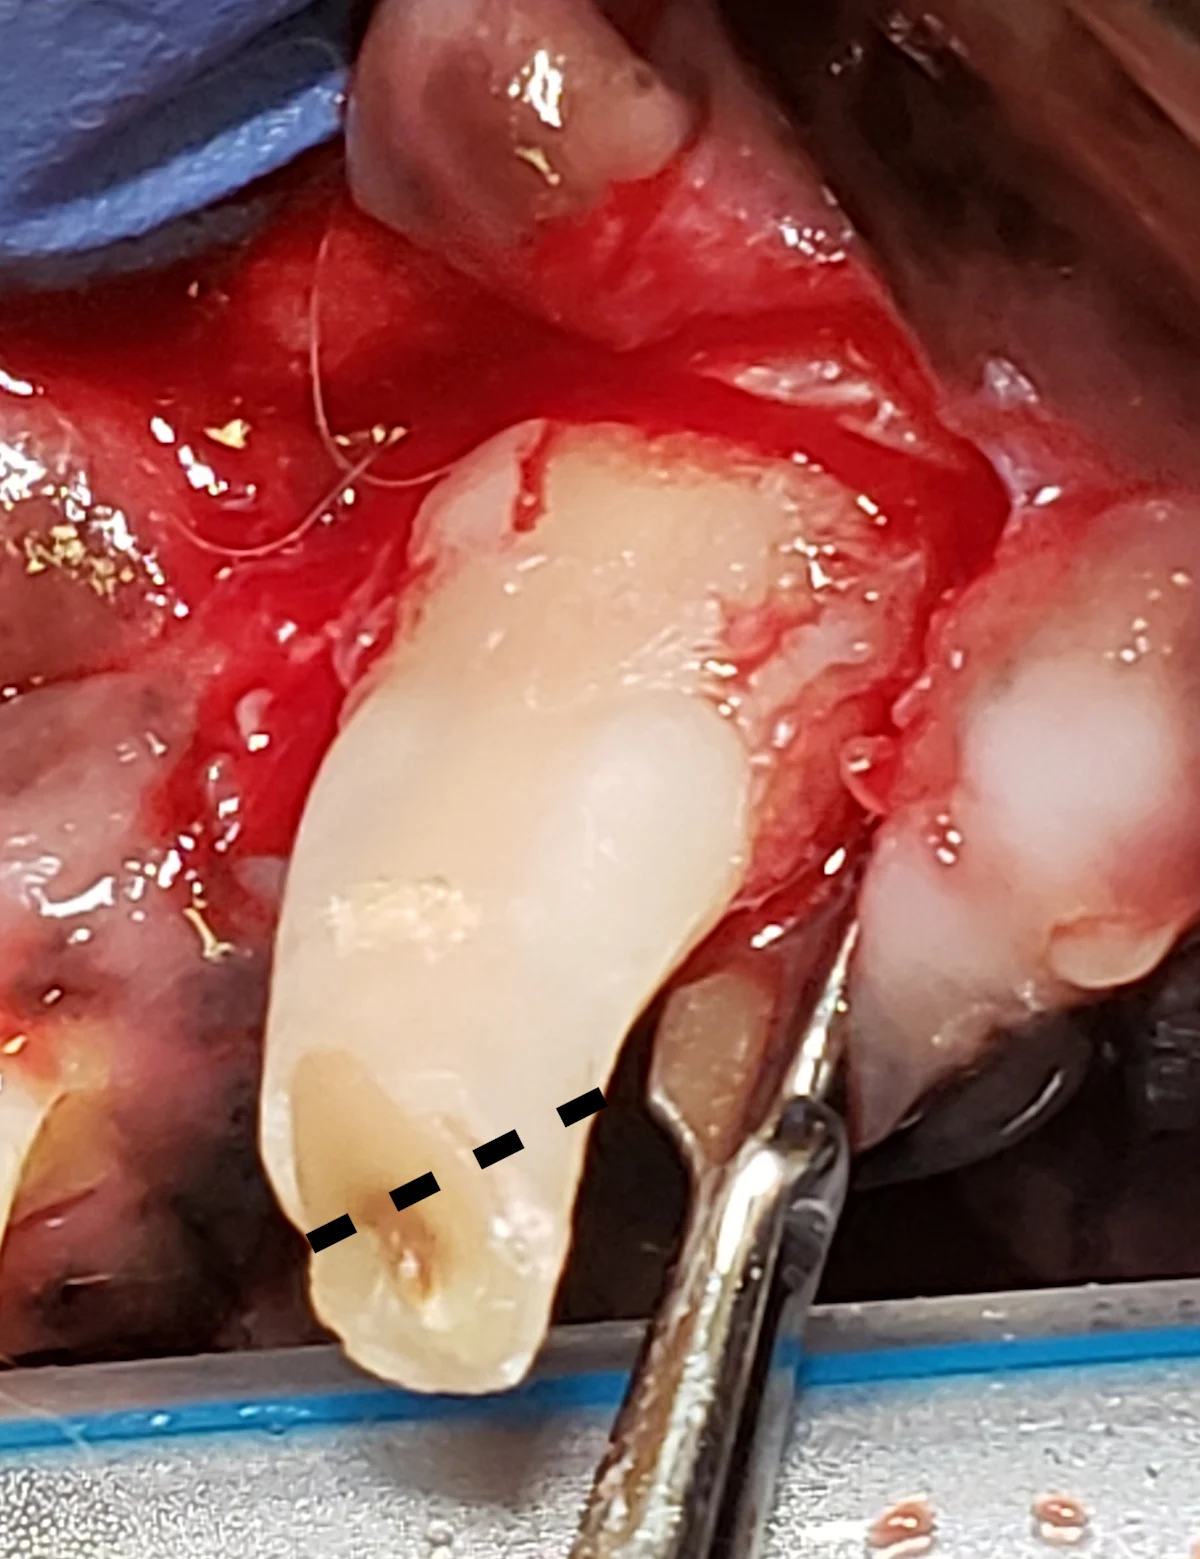

Step 7: Fatigue the Periodontal Ligament (Elevation)

Advance the blade edge of a winged elevator (sized appropriately for the diameter of the tooth root) using controlled apical force, with the tip of the elevator just past the fingertip grip. When positioned in the periodontal ligament space, rotate the elevator to engage the side or edge of the tooth surface, stretching the periodontal ligament. Apply slow, steady pressure for 5 to 10 seconds.

Author Insight

Although a rocking motion may be preferred over slow, steady pressure in some cases, this may result in a force that is not as effective, and care should be taken not to apply too much pressure. Winged elevators are primarily used on the mesial and distal aspects of maxillary canine teeth. If the entire crown is present, the curved portion may interfere with the ability to place the dental elevator in a straight line to access the distal periodontal ligament space. A portion of the crown may be removed to avoid this obstruction (dotted line).